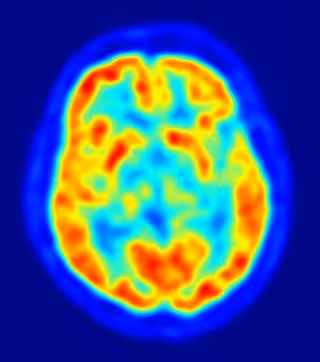

Foto: JENS LANGNER